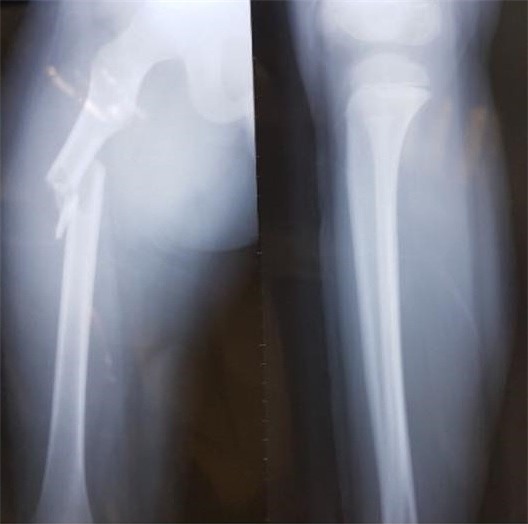

Hình ảnh khi xương đùi của học sinh Trần Chí Kiên được chụp X-quang. Ảnh: NVCC.